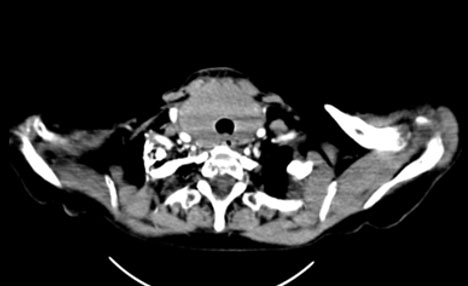

Fourteen years later, the patient presented to our institution with a palpable cervical mass. A total body CT revealed a non-enhancing diffusely enlarged hypodense thyroid gland without the presence of enlarged lymph nodes or other significant abnormalities (Figure 3). A magnetic resonance (MR) examination of the neck done one month later showed a rapid increase in size of the thyroid gland demonstrating diffuse enhancement postgadolinium administration and restricted diffusion. It showed to exert mass effect on the surrounding structures and significant narrowing of the airways. No pathological lymph nodes were seen (Figure 4, Figure 5, Figure 6). Because of the patient’s previous history of lymphoma and rapid growth of the thyroid gland, the possibility of extra-nodal thyroid lymphoma recurrence was raised, and a core needle biopsy of the thyroid gland was done and sent to pathology which confirmed the presence of diffuse large B-cell lymphoma within the thyroid gland.

Figure 3: Axial CT image (2025) showing a non-enhancing diffusely enlarged hypodense thyroid gland without the presence of enlarged lymph nodes.